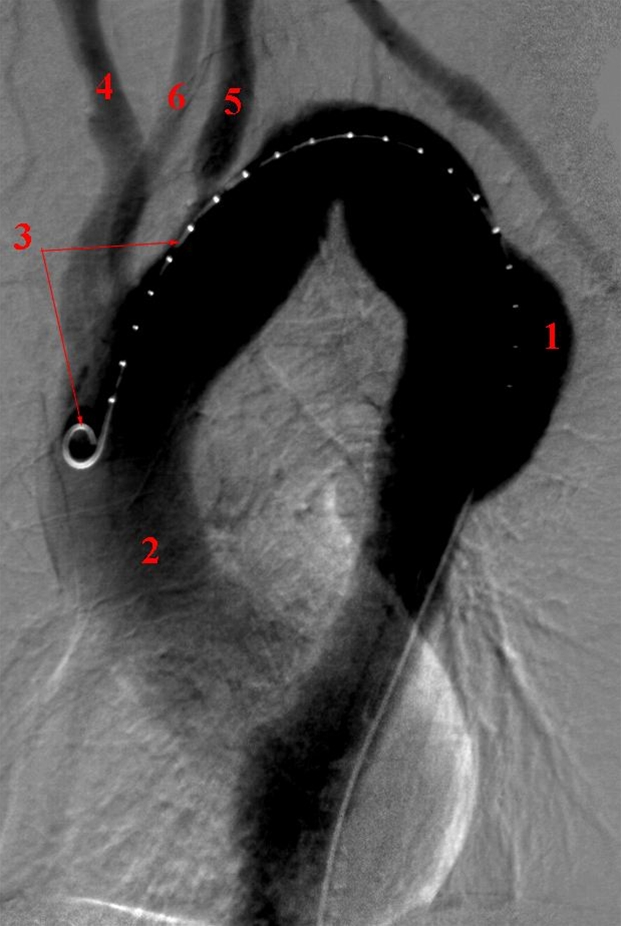

Arteriografi af aorta thoracalis (røntgenkontrastundersøgelse af legemspulsåren i brystet). Gennem kateter indført fra lysken indsprøjtes røntgenkontrastvæske, der fordeler sig i legemspulsåren i brysthulen, hvor der ses et aneurisme (udposning).

1. Aneurisme i aorta descendens der måler maksimalt 4 cm i diameter

2. Aorta ascendens

3. Endovaskulært kateter indført via punktur i lysken (via a. femoralis)

4. Truncus brachiocephalicus

5. Venstre a. subclavia (pulsåre til armen)

6. Venstre a. carotis communis (halspulsåre)